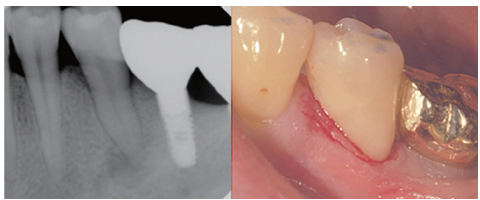

Figure 1

Preoperative periapical view and clinical photograph. (a) Periapical radiolucency on #35; (b) Cervical abrasion.

Figure 5

Periapical view and clinical photograph after class V Resin filling.

Figure 1 Preoperative periapical view and clinical photograph. (a) Periapical radiolucency on #35; (b) Cervical abrasion.

Figure 5 Periapical view and clinical photograph after class V Resin filling.